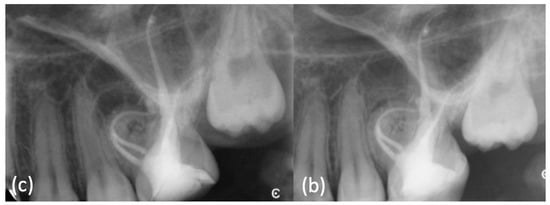

An extraoral examination did not reveal abnormalities. An intraoral examination showed an aberrant coronal anatomy of element 12: the crown was wider mesially, with a slight irregularity of the incisal edge, hence a dens invaginatus was suspected (Figure 1a); no caries or restoration were detected.

(a) Intraoral examination showed a wide crown of element 1.2, typical anatomy of a dens invaginatus. (b) Periapical X-ray showed a mesial invagination separated from the main distal canal (dens invaginatus type3a), with an apical radiolucent area. (c) CBCT confirmed these findings.

Imaging examination and diagnosis: A long cone periapical (LCPA) X-ray (Figure 1b) was taken (X-minD™ Unity, ACTEON® IMAGING, Merignac, France). Dens invaginatus type3a anatomy [35] was confirmed and chronic apical periodontitis was diagnosed, with a radiolucent area on the mesial aspect of the root, laterally to the main canal, where the invagination was communicating with the periodontal ligament through a pseudo-foramen; a large periapical radiolucency surrounded the periapex.

A small-FOV CBCT (Orthophos XG 3D, Dentsply Sirona, Charlotte, VA, USA) (Figure 1c–Movie 1) was taken as a supporting examination. The axial slices confirmed that the main root canal, developing from a small distal chamber, was separated from the invagination at all levels; furthermore, it showed that the invagination was limited to the root, not involving the clinical crown of the tooth, the periapical lesion was present both at the main and the pseudo-foramina and that it had perforated both the buccal and the palatal cortical plate.